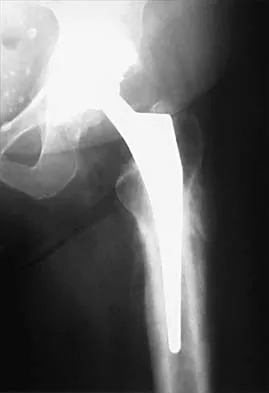

Figure 17 shows the radiograph of an 80-year-old woman who has left groin pain. She underwent a total hip arthroplasty 15 years ago and has no history of hip dislocation; however, she now reports that the pain results in functional impairment. Preoperative findings reveal that the component used has been discontinued, the locking mechanism is poor, and there is no replacement polyethylene available from the company. During surgery, the acetabular component is found to be well fixed, it is in satisfactory position, and adequate access can be obtained through the screw holes in the component to debride the osteolytic cavities. What is the best course of action for revision?